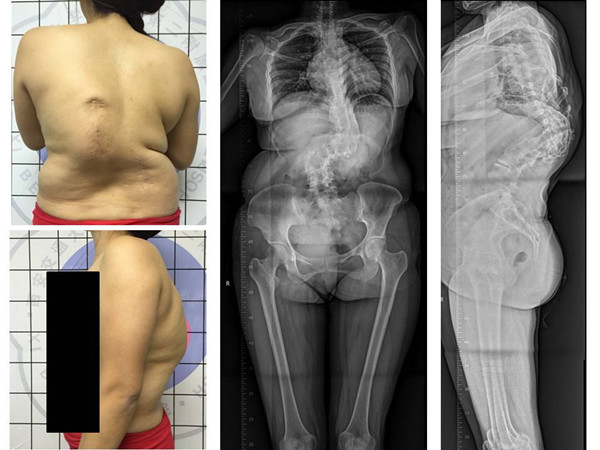

术前外观照及X线正侧位

来自我省咸阳市的患者张某,因胸腰部脊柱畸形30余年,腰部疼痛1月慕名来我院求诊。患者为成年女性,诊断为先天性脊柱侧弯。病程长,儿时有过手术史,侧弯Cobb角度超过90度。入院后科内反复讨论,研读患者的影像学资料,并采用3D打印重现患者脊柱骨性结构(1:1)。在此基础上,制定了详细的术前计划及整体治疗方案。治疗过程中,采取骨性牵引2周,缓解手术矫形时神经肌肉血管的张力,降低手术风险,手术当天,由贺西京教授主刀,李浩鹏教授,王栋副教授,赵波、秦杰主治医师、王放住院总医师密切配合,在麻醉科及手术室的协助下,施行截骨矫形手术。术中诱发电位监护、自体血回输,唤醒试验、中心静脉压、外周动脉压监护、保温毯等措施保护患者的生命安全及神经功能。患者畸形严重,手术非常复杂,稍有不慎即有可能导致瘫痪,给患者和家属带来严重负担。贺西京教授、李浩鹏教授、王栋副教授等手术麻醉人员全神贯注,一丝不苟,连续手术8小时,患者脊柱畸形明显纠正,侧凸Cobb角纠正至20°,生命体征及神经功能完好,患者截骨矫形手术顺利完成。术后在我科护理和我院康复科医师的精心护理康复下,患者1周下地站立行走,顺利康复。术后无明显并发症,患者及家属对手术效果非常满意,现已出院。

先天性脊柱侧弯在骨科属于常见病,好发于青少年,早期手术效果好,若错过了最佳治疗时机,侧弯进展迅速,畸形发展严重,严重影响患者的身心健康。本例患者就是典型的错失治疗时机的病例,发展至成年时,畸形已经很严重、僵硬,大大增加了治疗难度及风险。